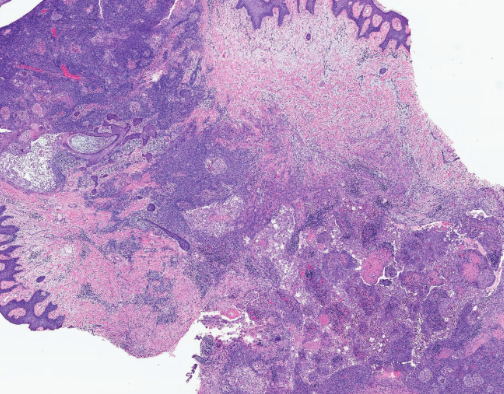

Χρώση αιματοξυλίνης-ηωσίνης. Παρουσία διάσπαρτων άτυπων μιτωτικών φιγούρων, νεκρωτικών νεοπλασματικών κυττάρων και τυπικής σμηγματώδους διαφοροποίησης με κενοτοπιώδες κυτταρόπλασμα και κυματοειδή πυρηνικά περιγράμματα (Ευγενική παραχώρηση Dr. V. Penopoulos)